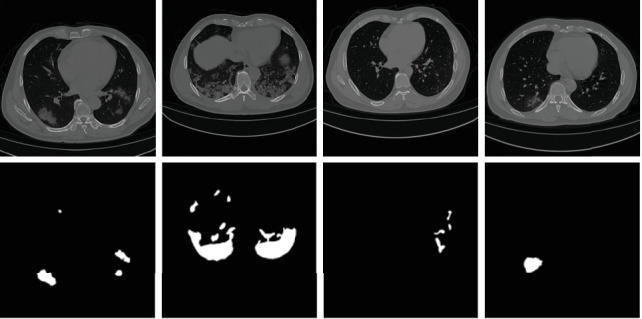

Accurate segmentation of COVID-19 CT images is crucial for reducing the severity and mortality rates associated with COVID-19 infections. In response to blurred boundaries and high variability characteristic of lesion areas in COVID-19 CT images, we introduce CDSE-UNet: a novel UNet-based segmentation model that integrates Canny operator edge detection and a Dual-Path SENet Feature Fusion Block (DSBlock). This model enhances the standard UNet architecture by employing the Canny operator for edge detection in sample images, paralleling this with a similar network structure for semantic feature extraction. A key innovation is the DSBlock, applied across corresponding network layers to effectively combine features from both image paths. Moreover, we have developed a Multiscale Convolution Block (MSCovBlock), replacing the standard convolution in UNet, to adapt to the varied lesion sizes and shapes. This addition not only aids in accurately classifying lesion edge pixels but also significantly improves channel differentiation and expands the capacity of the model. Our evaluations on public datasets demonstrate CDSE-UNet's superior performance over other leading models. Specifically, CDSE-UNet achieved an accuracy of 0.9929, a recall of 0.9604, a DSC of 0.9063, and an IoU of 0.8286, outperforming UNet, Attention-UNet, Trans-Unet, Swin-Unet, and Dense-UNet in these metrics.